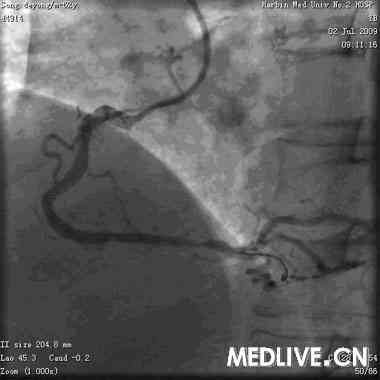

3.PCI处置: 植入支架(3.5*24)一枚

.PCI术后:(图4:支架后)

5

.复查OCT示:支架贴壁良好(图5)

图4 PCI处置

图5 术后恢复良好